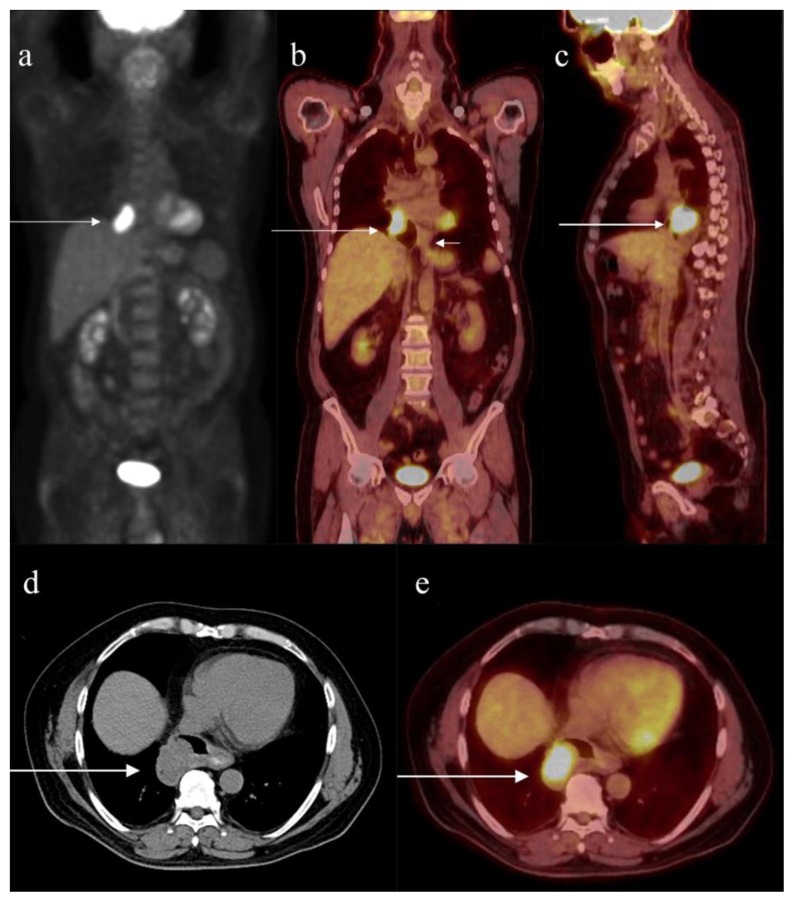

Endoscopic ultrasound (EUS) was done with 5 MHz radial echoendoscope. The EUS revealed hypoechoic mass in the diverticulum (Fig 2). The mass did not invade the mediastinum. Endoscopic biopsy showed squamous cell carcinoma. He subsequently underwent Fluorine-18-2-Fluoro-2-Deoxy-D-Glucose Positron Emission Tomography and Computed Tomography (FDG-PET/CT) which showed a hypermetabolic mass lesion measuring 3.6 × 3.1 × 3.4 cm within the diverticulum measuring 4.8 × 4.8 × 5.4 cm, arising from the distal esophagus (Fig 3); the average standardized uptake value (SUV) was 10.2 and maximal SUV was 14.8. PET/CT showed no evidence of regional lymphadenopathy or metastatic disease.

Figure 3.

62 year old male with carcinoma in esophageal diverticulum. A) Maximum intensity projection of FDG PET scan showing the hypermetabolic lesion with average SUV 10.2 and maximal SUV 14.8, in the region of right cardiophrenic angle (arrow). PET scanning of the body from the skull base to the upper thighs was performed 90 minutes after administration of 14.57 milli-Curie Ci of F18 FDG intravenously. Helical CT from the skull base to the upper thighs with 4 mm axial slices with dilute barium as oral contrast and without intravenous contrast was also performed and used for PET attenuation correction and localization. The PET images were reconstructed in axial, sagittal, and coronal planes and were fused with the reconstructed CT images in axial, sagittal, and coronal planes.

B) Coronal fused FDG-PET/CT showing the hypermetabolic lesion within the epiphrenic diverticulum (long arrow). Short arrow shows the esophago-gastric junction.

C) Sagittal fused FDG-PET/CT showing the hypermetabolic lesion within the epiphrenic diverticulum (arrow).

D) Axial image of CT portion of FDG-PET/CT showing the mass (arrow) measuring 3.6 × 3.1 × 3.4 cm within the epiphrenic diverticulum measuring 4.8 × 4.8 × 5.4 cm.

E) Axial fused FDG-PET/CT showing the hypermetabolic mass (arrow) measuring 3.6 × 3.1 × 3.4 cm, with average SUV 10.2 and maximal SUV 14.8, within the epiphrenic diverticulum.